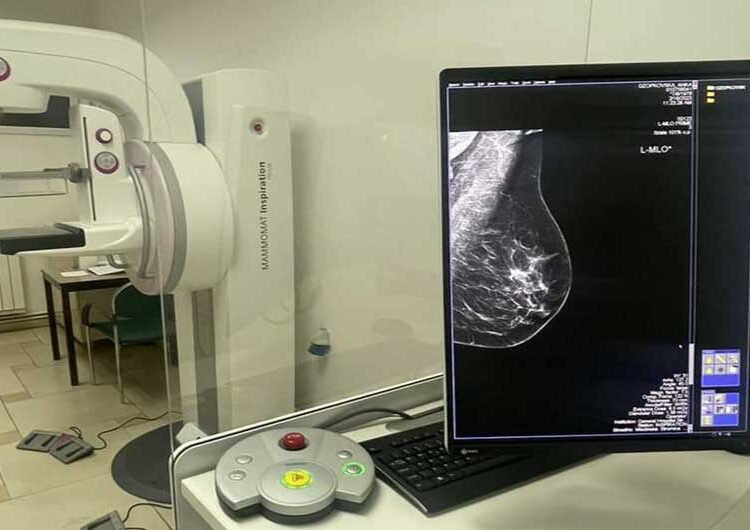

Од ЈЗУ „Општа Болница“ во Струмица информираат дека во моментот се работи на реконструкција на Одделот за Рентгендијагностика како и подготовка на просторот со градежни активности, каде треба да биде сместена нова опрема. Завршена е инсталацијата и подготовките за работа на нов дигитален Мамограф и нов модерен Ултразвук за ехо на дојка.

„Конечно обезбедивме нов дигитален Мамограф и модерен Ултразвук за ехо на дојка, затоа што знаеме колку е тоа важно во превенирање, рано откривање и дијагностицирање на карцином на дојка кое е едно од трите најчести малигни заболувања кај жените во Македонија. Од наредната недела започнуваме да работиме со закажување преку „Мој термин“ во Кабинетот за ЕХО на ДОЈКА и МАМОГРАФИЈА. Продолжуваме да работиме посветено се во интерес на нашите пациенти“ – стои во соопштението од ЈЗУ „Општа Болница“ Струмица, најавувајќи дека во наредните денови се очекува да заврши и реконструкцијата на просторот и инсталацијата на новиот дигитален РТГ апарат.